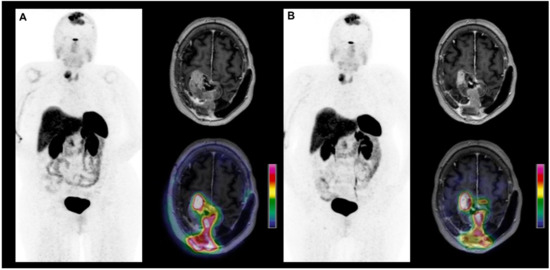

3.3.1. PRRT in Meningiomas

- Seystahl, K.; Stoecklein, V.; Schüller, U.; Rushing, E.; Nicolas, G.; Schäfer, N.; Ilhan, H.; Pangalu, A.; Weller, M.; Tonn, J.-C.; et al. Somatostatin-receptor-targeted radionuclide therapy for progressive meningioma: Benefit linked to 68Ga-DOTATATE/-TOC uptake. Neuro-Oncology 2016, 18, 1538–1547. [Google Scholar] [CrossRef]